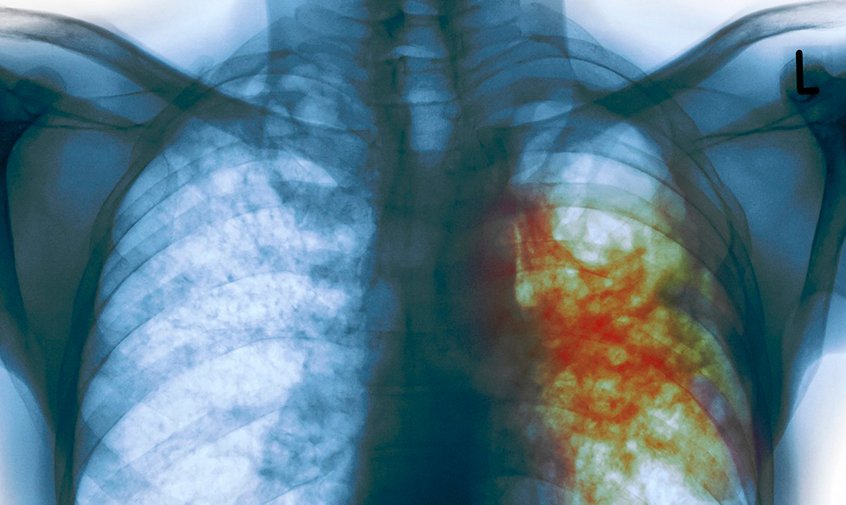

-- Статистикага таянсак, Кыргызстанда жыл сайын 5500 адам кургак учук оорусу менен катталат. Жылына балдар жана өспүрүмдөр арасында кургак учуктун 900 учуру аныкталат. Ал эми 500 адам аталган дарттан каза табат. Оорулуулардын 75%ы 20-40 жаштагы адамдар. Негизи жер шаарынын калкынын үчтөн бир бөлүгү кургак учук бактерияларын жуктуруп алышат. Бирок, жуктуруп алган иммунитети төмөндөгөн адамдарда 5-10%  гана кургак учук өнүгөт. Өспүрүмдөр жана кары-картаңдар инфекцияга көбүрөөк кабылышат. Кургак учук – бул инфекциялык аба тамчы жолу аркылуу жуга турган олуттуу, жугуштуу оору. Негизинен бүт органдарды, анын ичинен өпкөнү жабыркатат. Ал жөтөлгөндө, чүчкүргөндө, какырганда, түкүргөндө  жугат. Андыктан эч ким кургак учук  жуктуруп алуудан корголгон эмес. Кургак учук менен ооруган адам жылына 10-15 адамга жуктурушу мүмкүн. Бул оору Кыргызстанда эле эмес, дүйнө жүзү боюнча актуалдуу көйгөйлөрдүн бири. Анын алгачкы белгилери: эки жумадан ашык жөтөлүү, тамакка болгон табиттин жоголушу, салмактын төмөндөшү, дене табынын көтөрүлүшү, өзгөчө түнкүсүн тердөө, көкүрөктүн оорушу жана кан аралаш какырык чыгаруу (түкүрүү).

-- Болот. Бирок, дарыгерге эртерээк кайрылып, дарылоону үзгүлтүксүз жүргүзсө. Дарылануу мөөнөтү медициналык кызматкерлердин кароосунда кеминде 6-8 айга чейин созулат.  Дарыланууну үзгүлтүккө учуратуу кургак учуктун дарыларга туруктуу түрүнүн өнүгүшүнө алып келет. Дарылоо 24-28 айга чейин жүргүзүлөт. Кургак учукту какырыктын микроскопия анализи, рентгенге тартуу менен аныктаса болот. Ал эми балдарда бул ооруну аныктоо үчүн “манту” пробасын коюп, эмдөө зарыл. Адам ден соолукка кайдыгер мамиле кылганда иммунитети түшүп кетет. Ал эми иммундук системасы начар адамга оору дароо эле жугат. Ошондой эле көчөдөгү түкүрүк кургак учуктун булагы катары каралат. Жерге түшкөн түкүрүккө күндүн нуру тийсе жакшы, андагы микробдор өлөт. Бирок, ал көлөкөдө же нымдуу жерде калса, улам кургаган сайын чаң кошулуп, микробдор абага көтөрүлөт. Аба аркылуу соо адамдарга жугат. Аталган ооруга кабылган адамдар күчтүү дары-дармек колдонууга мажбур болушат. Бул убакта тамакты да күчтүүлөп ичүүсү зарыл. Кургак учукка кабылган кош бойлуу аялдын баласы дагы аталган оору менен ооруп калышы ыктымал. Бирок, кургак учук  тукум куубайт.